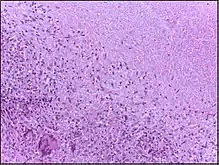

| Micrograph showing caseous necrosis of a tuberculous lymph node. H&E stain. Histological specimens are normally obtained from supraclavicular lymph nodes to demonstrate caseous necrosis. | |

In caseous necrosis no histological architecture is preserved (unlike with coagulative necrosis).[5][6] On microscopic examination with H&E staining, the area is acellular, characterised by amorphous, roughly granular eosinophilic debris of now dead cells,[6] also containing interspearsed haematoxyphilic remnants of cell nucleus contents.[5] This caseus necrotic center is enclosed within a granuloma.[6][7]